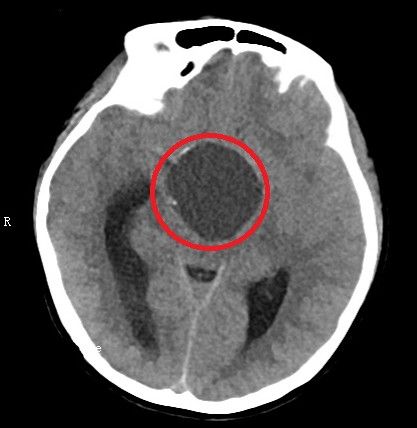

术后头部ct显示:鞍区肿瘤基本切除干净。(红圈内为手术区域)

11月22日,黄萌异主任医师、陈磊副主任医师等在全麻下为小雯施行显微镜下经终板池入路颅咽管瘤切除术,成功拔除这个“不定时炸弹”。术后第四天,小雯就能正常进食,术后第六天转回普通病房,并于1213日康复出院。